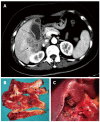

Methods: From July 2008 to June 2014, a total of 142 cases of pathologically diagnosed XGC were reviewed at our hospital, among which 42 were misdiagnosed as gallbladder carcinoma (GBC) based on preoperative radiographs and/or intra-operative findings. The clinical characteristics, preoperative imaging, intra-operative findings, frozen section (FS) analysis and surgical procedure data of these patients were collected and analyzed.

Results: The most common clinical syndrome in these 42 patients was chronic cholecystitis, followed by acute cholecystitis. Seven (17%) cases presented with mild jaundice without choledocholithiasis. Thirty-five (83%) cases presented with heterogeneous enhancement within thickened gallbladder walls on imaging, and 29 (69%) cases presented with abnormal enhancement in hepatic parenchyma neighboring the gallbladder, which indicated hepatic infiltration. Intra-operatively, adhesions to adjacent organs were observed in 40 (95.2%) cases, including the duodenum, colon and stomach. Thirty cases underwent FS analysis and the remainder did not. The accuracy rate of FS was 93%, and that of surgeon's macroscopic diagnosis was 50%. Six cases were misidentified as GBC by surgeon's macroscopic examination and underwent aggressive surgical treatment. No statistical difference was encountered in the incidence of postoperative complications between total cholecystectomy and subtotal cholecystectomy groups (21% vs 20%, P > 0.05).